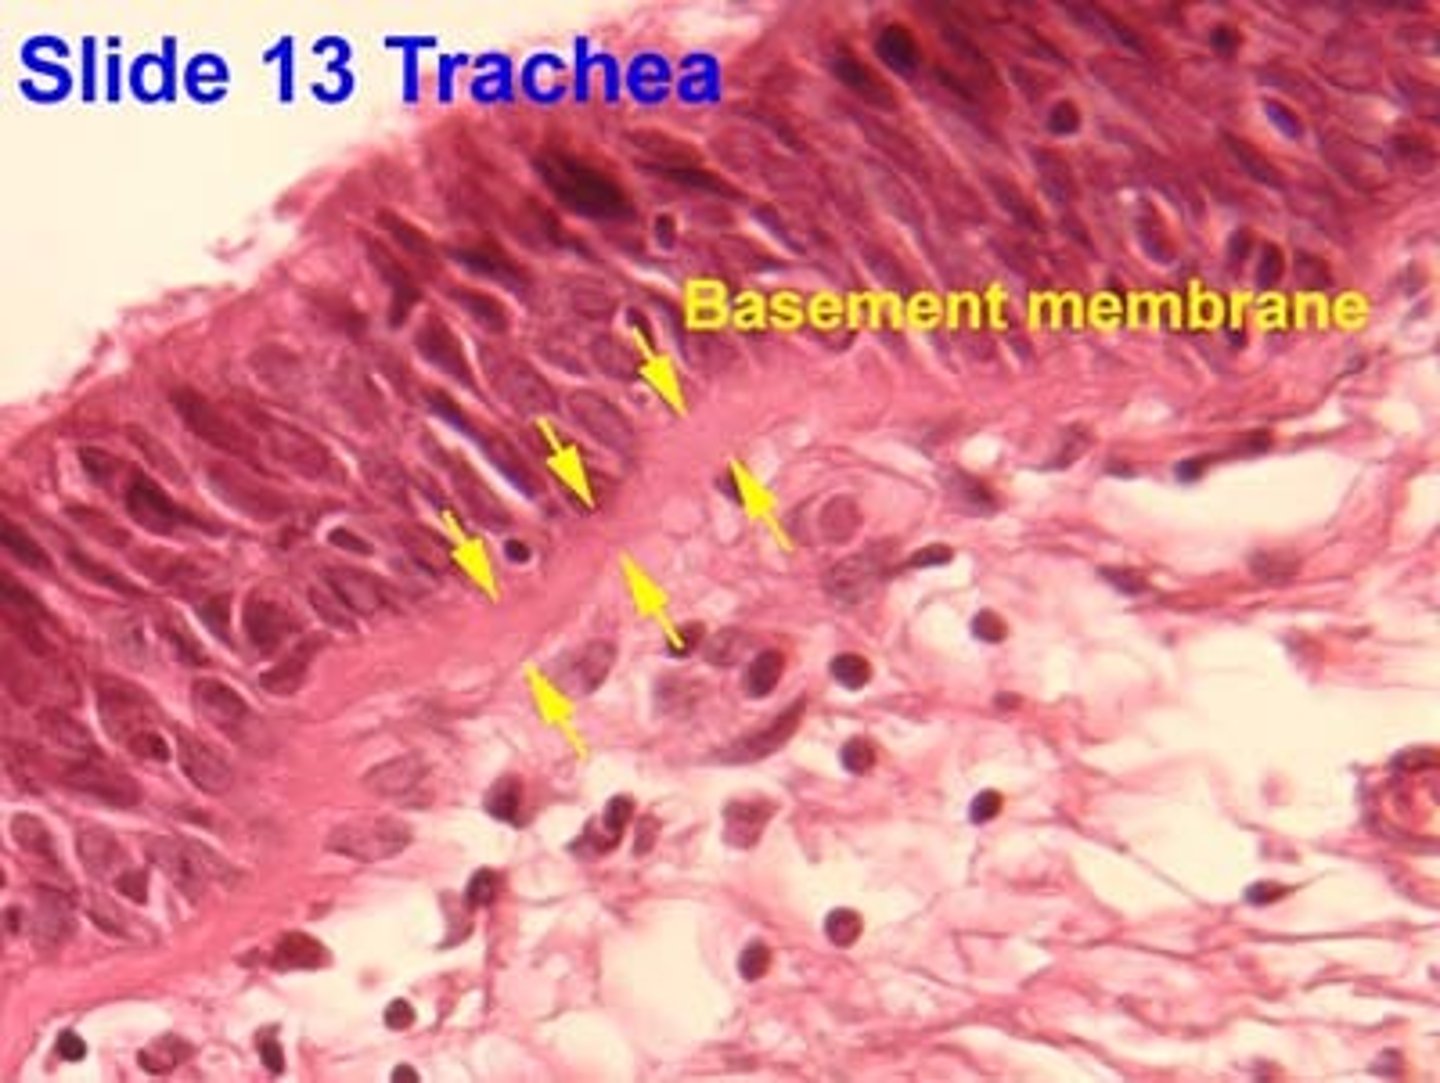

Why does the basement membrane appear thick and glossy?

Densely packed collagen fibers below basal lamina.

What is characteristic of the lamina propria in the trachea?

Very cellular loose CT with BALT.